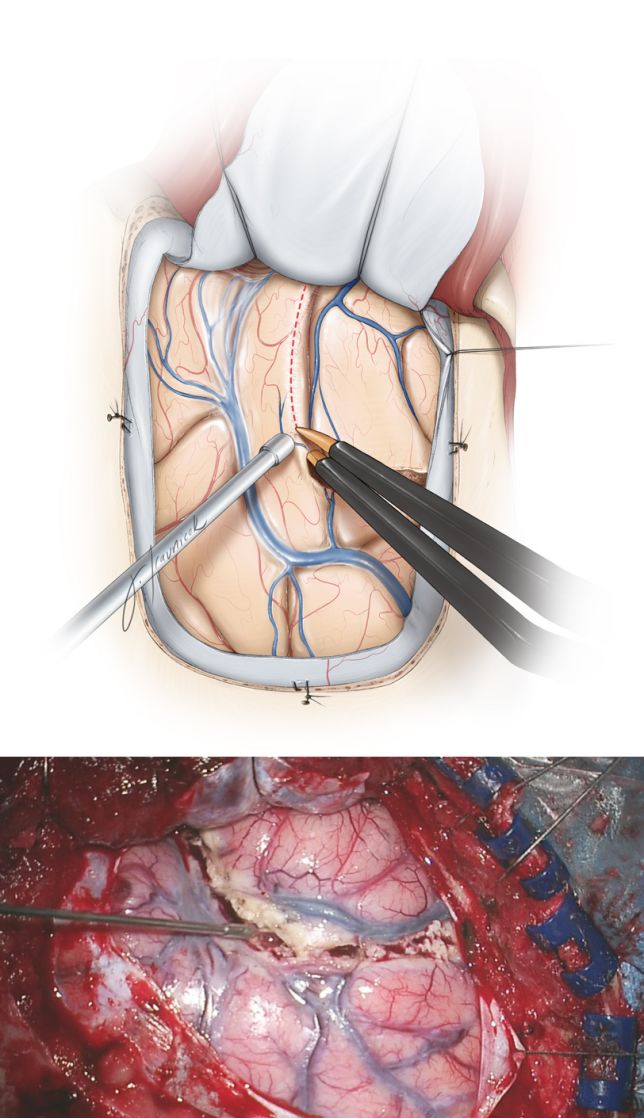

图9. 笔者应用1#penfield剥离子来测量确定颞叶切除范围,在剥离子上标出了4.0cm标志(如图),然后从颞中回上方向前滑入,直至剥离子前端碰到蝶骨翼紧下方的颞前窝。颞叶切除范围在皮层标记,避免损伤Labbe静脉。颞叶皮质切除范围优势侧约为3.5cm,非优势侧约为4cm。

图10. 沿颞上沟行皮质切除术。谨慎保留颞上回,因为优势侧颞叶可能支配语言功能。而后,从颞极向后3.5-4cm,垂直于颞中及颞下回长轴切除皮质。切除深度约为2-3cm,包括了梭状回。当术者经验丰富时,切除梭状回时可能会延伸地更靠近内侧至脑室水平,从而简化了颞角的暴露和及颞叶内侧结构的切除。术中导航可引导这一步操作。

笔者认为从外侧裂至蝶窦的桥静脉在颞前叶上,颞叶的回缩可引起这些静脉出血,术中应灼烧止血。

图11. 在颞前叶皮质上部和后部切除后行白质切除,以切断颞叶外侧皮质。中颅窝底往往有一个未名而恒定的骨性突起(黄色箭头),轻轻牵拉颞叶便可显露该解剖结构。此突起是指导白质离断的一个有用标志。颞叶上部、后部皮质切除及白质离断都应该和骨性突起考虑在一起,可确保术者不会贸然侵及颞角或损伤重要结构。

图12. 图示为颞角潜在位置与颞中回深部白质相关。颞角是显露和切除颞叶内侧结构的关键标识。颞角位于之前由颞中回覆盖的白质深处。进入脑室(双极尖端)见脑脊液流出及脉络丛辨识得以证实。确认进入脑室后,笔者切开脑室外侧壁以显露其内侧结构。

此处应该认识到,由于杏仁核占据了颞叶前内侧的空间,则实际脑室比预期更靠后。如果术者在皮质下解剖中迷失方向,可能会继续行内侧白质离断而完全忽略脑室并无意中进入大脑半球中心的脑干、丘脑或其他结构。